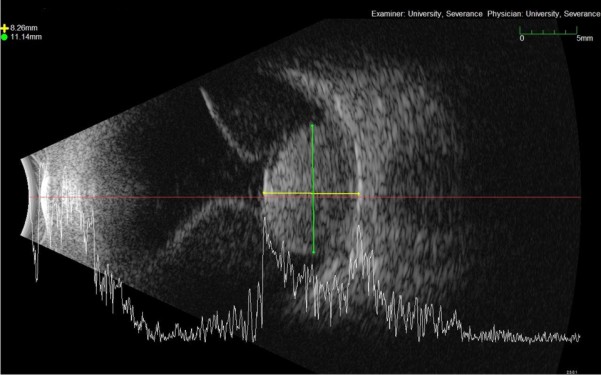

¾È±¸ ÃÊÀ½ÆÄ »çÁø. ¾È±¸ ÃÊÀ½ÆÄ °Ë»ç¸¦ ÅëÇØ ¾à 10mm Å©±âÀÇ ¸Æ¶ô¸· Èæ»öÁ¾ ¹× µ¿¹ÝµÈ Àå¾×¼º ¸Á¸·¹Ú¸®¸¦ È®ÀÎÇÒ ¼ö ÀÖ´Ù.